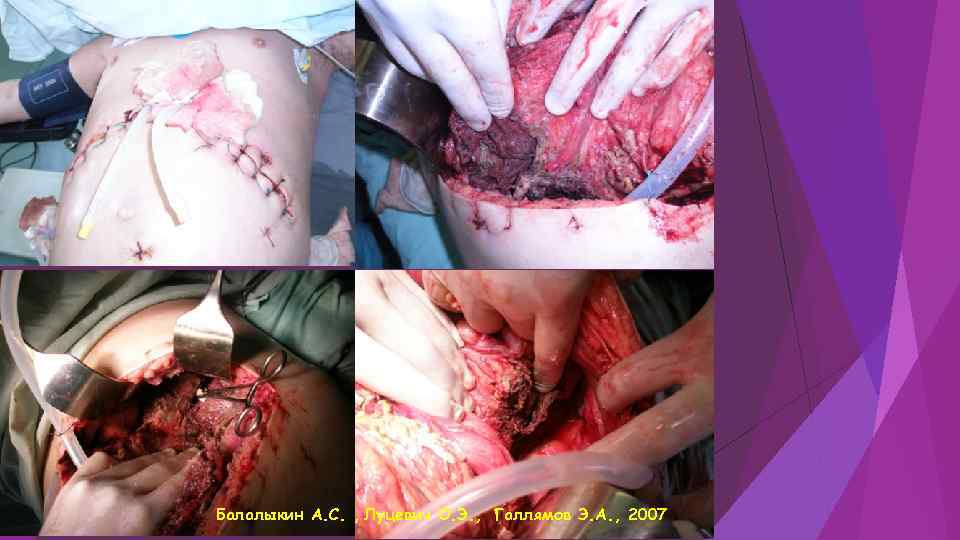

Балалыкин А. С. , Луцевич О. Э. , Галлямов Э. А. , 2007

Балалыкин А. С. , Луцевич О. Э. , Галлямов Э. А. , 2007

Балалыкин А. С. , Луцевич О. Э. , Галлямов Э. А. , 2007

Балалыкин А. С. , Луцевич О. Э. , Галлямов Э. А. , 2007

Этапная санация при распространенном деструктивном панкреонерозе Балалыкин А. С. , Луцевич О. Э. , Галлямов Э. А. , 2007

Этапная санация при распространенном деструктивном панкреонерозе Балалыкин А. С. , Луцевич О. Э. , Галлямов Э. А. , 2007

Этапная санация при распространенном деструктивном панкреонерозе Балалыкин А. С. , Луцевич О. Э. , Галлямов Э. А. , 2007

Этапная санация при распространенном деструктивном панкреонерозе Балалыкин А. С. , Луцевич О. Э. , Галлямов Э. А. , 2007